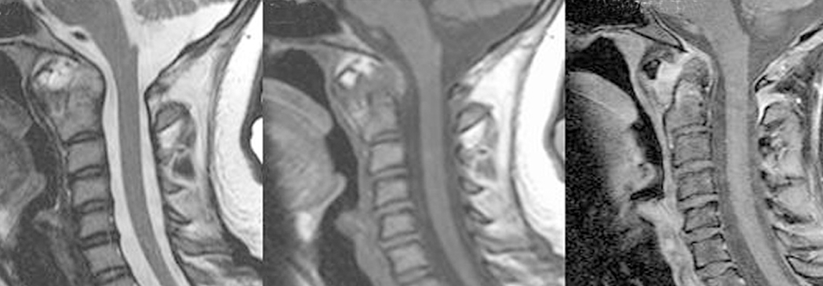

Die axiale Spondyloarthritis manifestiert sich bei Älteren oft an der Halswirbelsäule. Die axiale Spondyloarthritis manifestiert sich bei Älteren oft an der Halswirbelsäule. © wikimedia/James Heilmann, MD